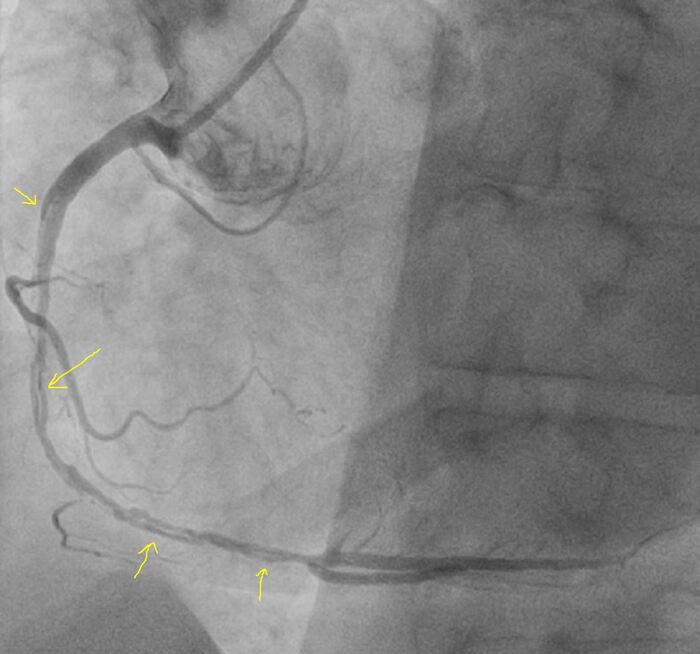

Левая коронарная артерия - незначимое поражение

Правая коронарная артерия - без значимого поражения, кровоток свободный

Контрастирование левого желудочка - обширная зона акинезии и дискинезии передне-боковой и части задней стенки, гиперкинез базальных отделов